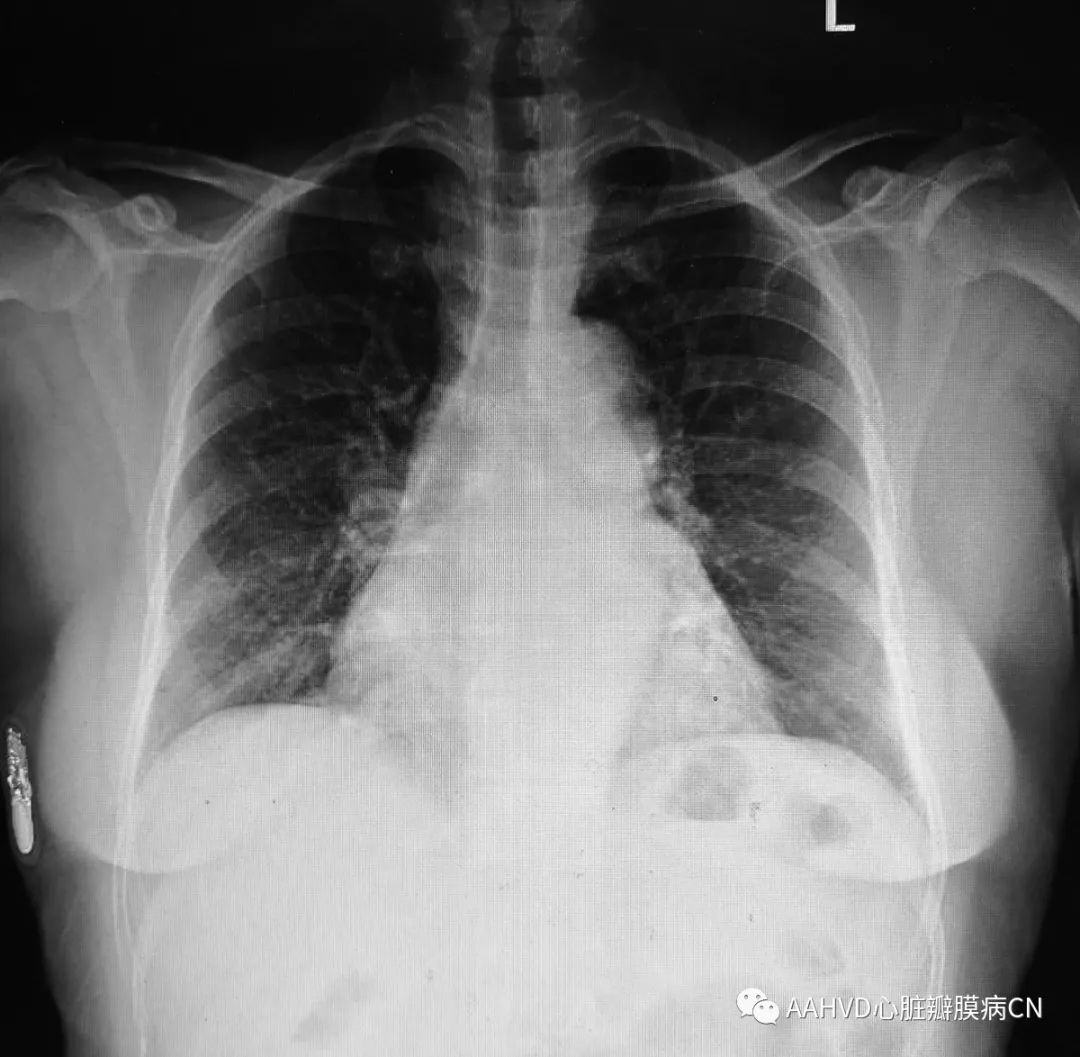

男性,39岁,主诉:胸闷气促10余年,加重不能平卧2月

手术日期:2018年11月30日

术前胸片

术前经胸超声:

风湿性心脏病,二尖瓣返流面积11.1cm²(重度返流),瓣口面积1.7cm²(轻度狭窄),前向流速101cm/s,主动脉瓣轻度狭窄并关闭不全。